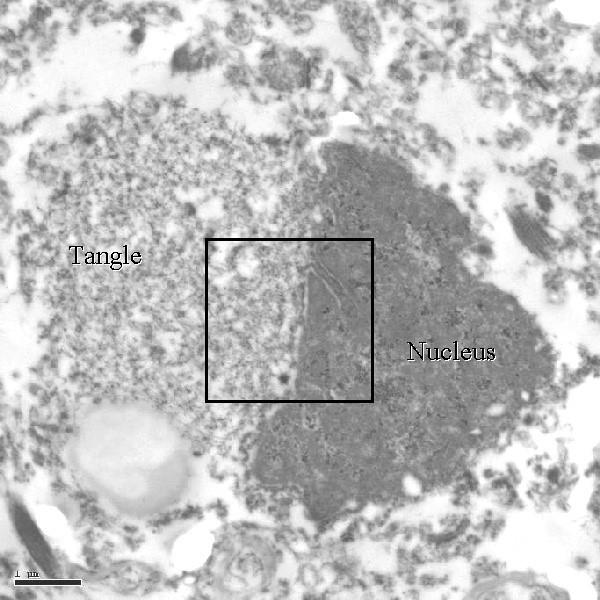

what is being shown here

plaques and tangles and beta amyloid of alzhemier's sieas

phosphorylated MTs around indivdiual neurons

what is being ponited out here

neurons with tangles displacing nucleus

what is a tangle

hyperphosphorylation of a neuron microtubule, causing it to precipitate